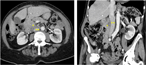

Immediate successful renal autotransplantation after proximal ureteral avulsion fallowing ureteroscopy: a case report

Mansor Alizadeh and others

Journal of Surgical Case Reports, Volume 2017, Issue 2, February 2017, rjx028, https://doi.org/10.1093/jscr/rjx028